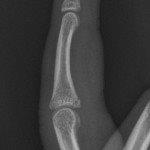

Mallet finger